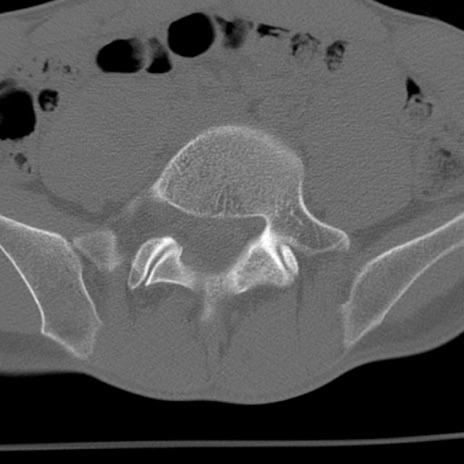

症例3 腰椎CT(横断像)

腰椎CT